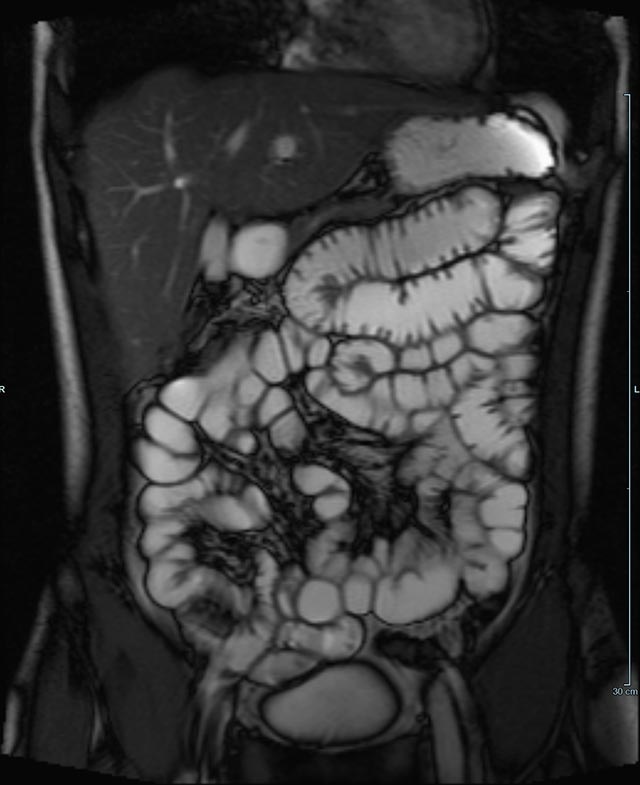

• Darm

• Darstellung bzw. Kontrolle im Verlauf bei perianalen Fisteln und Abszessen

• Verlaufskontrolle des Lokalbefundes nach Rektumentfernung bei Karzinom

Abdomen/Becken

• Leber

• Beurteilung von Lebervergrößerung und Leberverfettung

Abgrenzung gutartiger (z.B. Hämangiom, FNH oder Zysten) von bösartigen Lebererkrankungen (z.B. hepatozelluläres Karzinom, Metastasenverdacht)

• exakte Zuordnung krankhafter Prozesse zu einzelnen Lebersegmenten vor einer geplanten Operation.